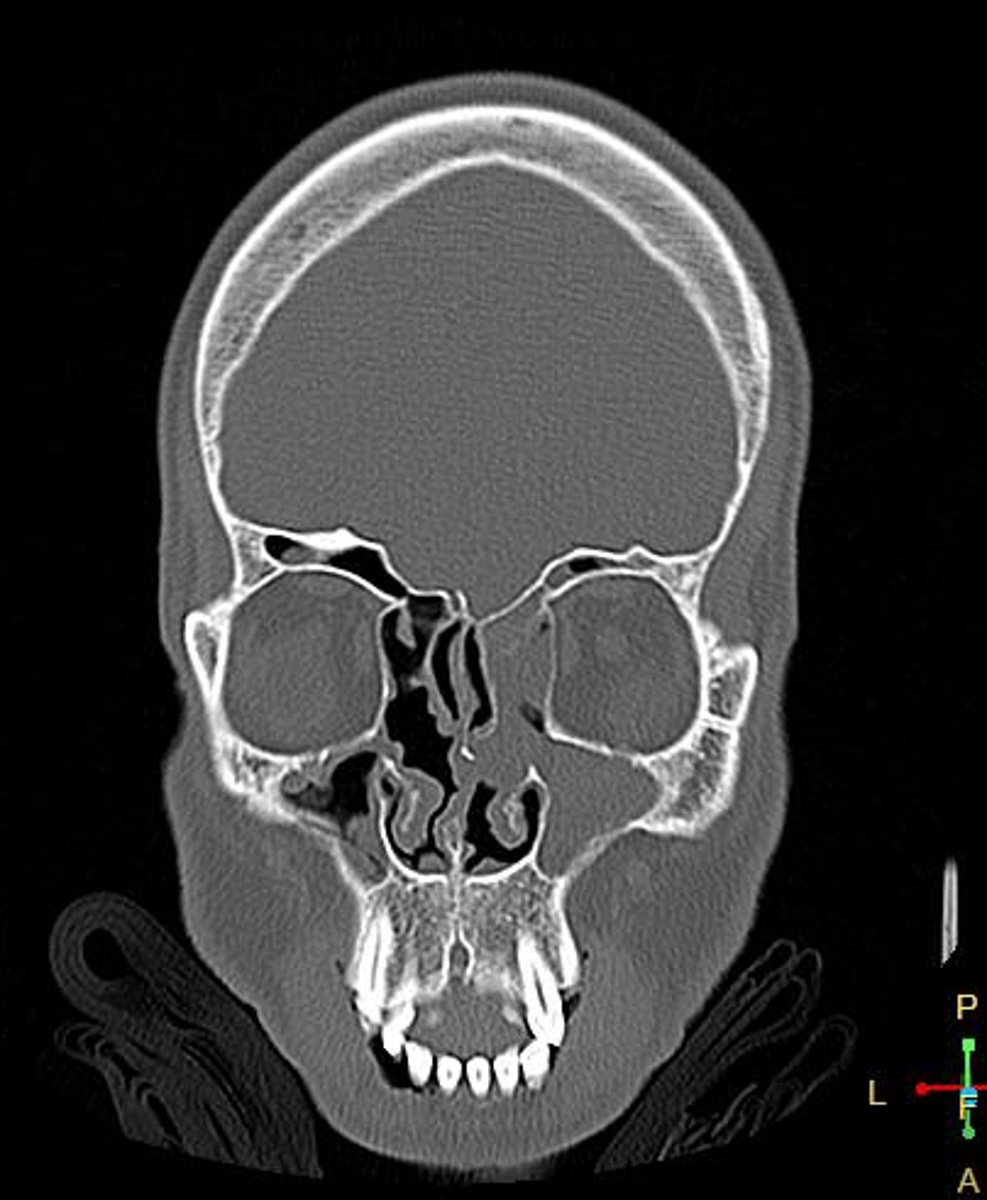

Paranasal sinus

What is the location of the lesion?

<p>What is the location of the lesion?</p>

Osteoma

Most likely diagnosis?

<p>Most likely diagnosis?</p>

Headaches

Concerns/complications?

<p>Concerns/complications?</p>

Refer to EENT

What is your next step?

<p>What is your next step?</p>